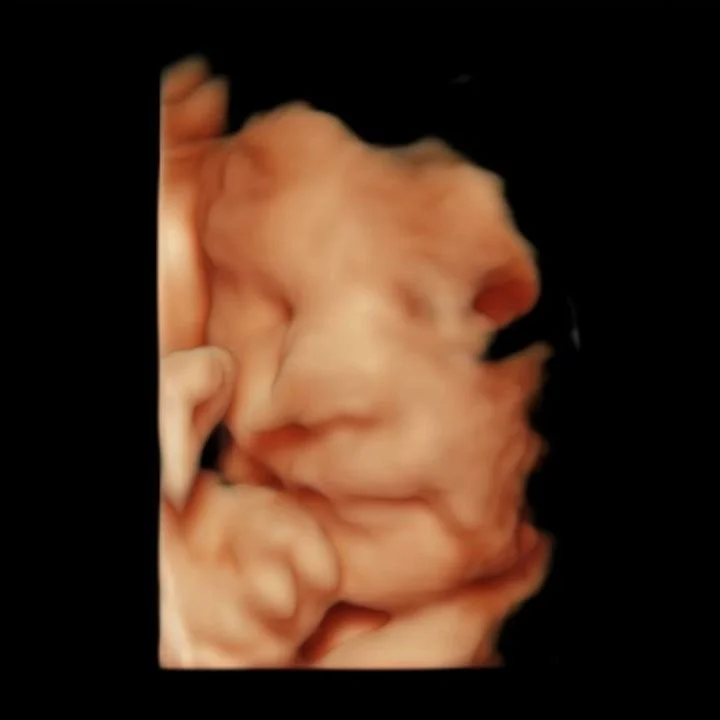

Our state of the art technology allows us to see your baby in a whole different way! With HD Live imaging, we can watch your baby wiggle, smile and yawn all in real time!